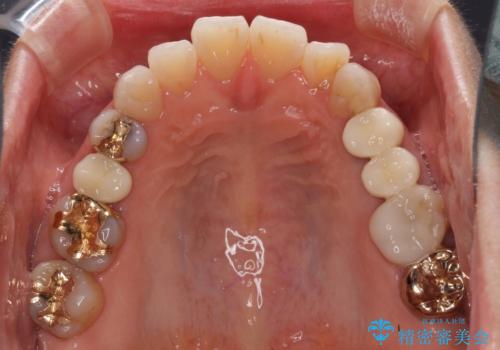

- 歯肉が退縮したためにクラウンの縁や歯根が見えてしまっていることを気にして来院された患者様です。

また、歯肉が黒く変色していることも気になるとのことでした。

仮歯に変える際に歯肉の一部を切除し、金属片による変色を除去した後、オールセラミッククラウンにて補綴することとしました。

メタルタトゥー(金属イオンの溶出による歯肉の変色)は、歯に装着された金属から金属イオンが溶け出したり、金属を除去するときの切削片が歯肉に入り込んでしまったりして引き起こされます。

物理的に除去をすることできれいな歯肉となりますが、残留している金属イオンにより再発するリスクがあります。